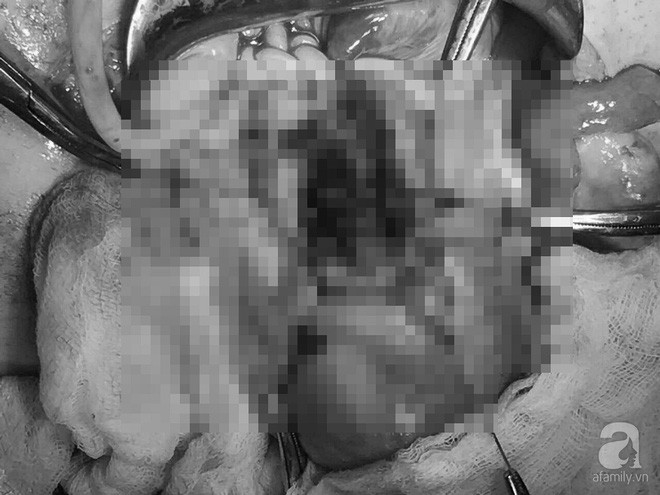

27/02/2018 20:50Thai lần 3 bám vào sẹo mổ cũ biến chứng, người phụ nữ 39 tuổi ở Cần Thơ suýt chết

Đó là trường hợp của chị Bùi Thị Tr. (39 tuổi, ngụ tại quận Ninh Kiều, thành phố Cần Thơ). Nhập viện trong tình trạng đau bụng nhiều kèm rong huyết gây thiếu máu sau hút thai ngoại viện 3 tuần, chị Tr. được thăm khám, siêu âm qua ngã âm đạo và xét nghiệm.

Các bác sĩ (BS) nhận định đây một trường thai bám ở sẹo mổ lấy thai có biến chứng. Bệnh nhân có vết mổ cũ lấy thai hai lần, hình ảnh trên siêu âm thấy khối nhau thai to, xâm lấn hết cơ tử cung vùng vết mổ, có nhiều mạch máu tăng sinh, tiên lượng có thể có tổn thương bàng quang. Tiến hành hội chẩn liên viện khẩn cấp, BS quyết định phẫu thuật để bóc khối thai bám sẹo mổ cũ.

Cuộc phẫu thuật diễn ra với sự phối hợp của ekip các BS Sản phụ khoa, Niệu khoa, Gây mê hồi sức, Huyết học truyền máu… Sau 1 giờ 20 phút phẫu thuật, khối thai với đường kính 6cm được bóc trọn khỏi sẹo mổ cũ, khâu phục hồi sẹo mổ và bảo tồn được tử cung cho bệnh nhân. Quá trình phẫu thuật, bệnh nhân đã được truyền 2 khối hồng cầu trước mổ để ổn định tình trạng thiếu máu. Hiện chị Tr. đã không còn đau bụng, hết chảy máu và đang hồi phục tốt.

BS CKII. Huỳnh Thanh Liêm, Trưởng khoa Sanh, Bệnh viện (BV) Phụ sản thành phố Cần Thơ cho biết: "Đây là một trường hợp nguy hiểm, khối thai bám sẹo mổ cũ có kích thước khá lớn, không thể điều trị nội khoa bảo tồn và nguy cơ mất máu nhiều trong phẫu thuật rất cao. Việc chẩn đoán và xử trí cần phải hết sức thận trọng cả về kỹ thuật khâu cầm máu xung quanh khối thai, bóc tách khối thai đồng thời phải đảm bảo phương tiện hồi sức tốt tại chỗ, ngân hàng máu phải sẵn sàng cho cuộc phẫu thuật".